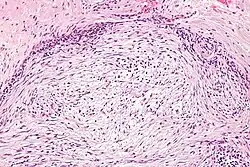

The microscopic histopathology of hematoxylin and eosin stained nodular fasciitis tumors consists of spindle-shaped myofibroblastic cells.[8] These cells are in a myxoid or a collagenous (high content of collagen fibers) tissue background. The neoplastic myofibroblasts are arranged in whorls and/or short bundles. These cells may show high rates of replicating as judged by their mitotic index, but these mitoses are normal in appearance. The tumor tissues often contain red blood cells, lymphocytes, and giant osteoclast-like cells, and may contain sites of bone-like tissue.[10] NF is sometimes classified into three subtypes based on its predominant histopathological pattern: myxoid or reactive (type I), cellular (type II), and fibrous (type III).[4] These patterns appear related to the duration of the lesion, with the myxoid variant tending to have the shortest duration and the cellular and fibrous variants tending to have progressively longer durations.[14] Immunohistochemical analyses indicate that the cells in NF usually express smooth muscle actin, muscle specific actin, and vimentin proteins but generally do not express CD34, S-100 protein, desmin, trypsin, factor VIII, F4/80, or HLA-DR1 proteins.[10] Uncommonly, the cells in NF tumors express the CD68 (a histiocyte-specific marker) protein.[4]

The histopathology and expressions of marker proteins in intravascular fasciitis tumors tend to be arranged in a storiformed or haphazard pattern and have vesicle-containing nuclei with prominent nucleoli.[6]